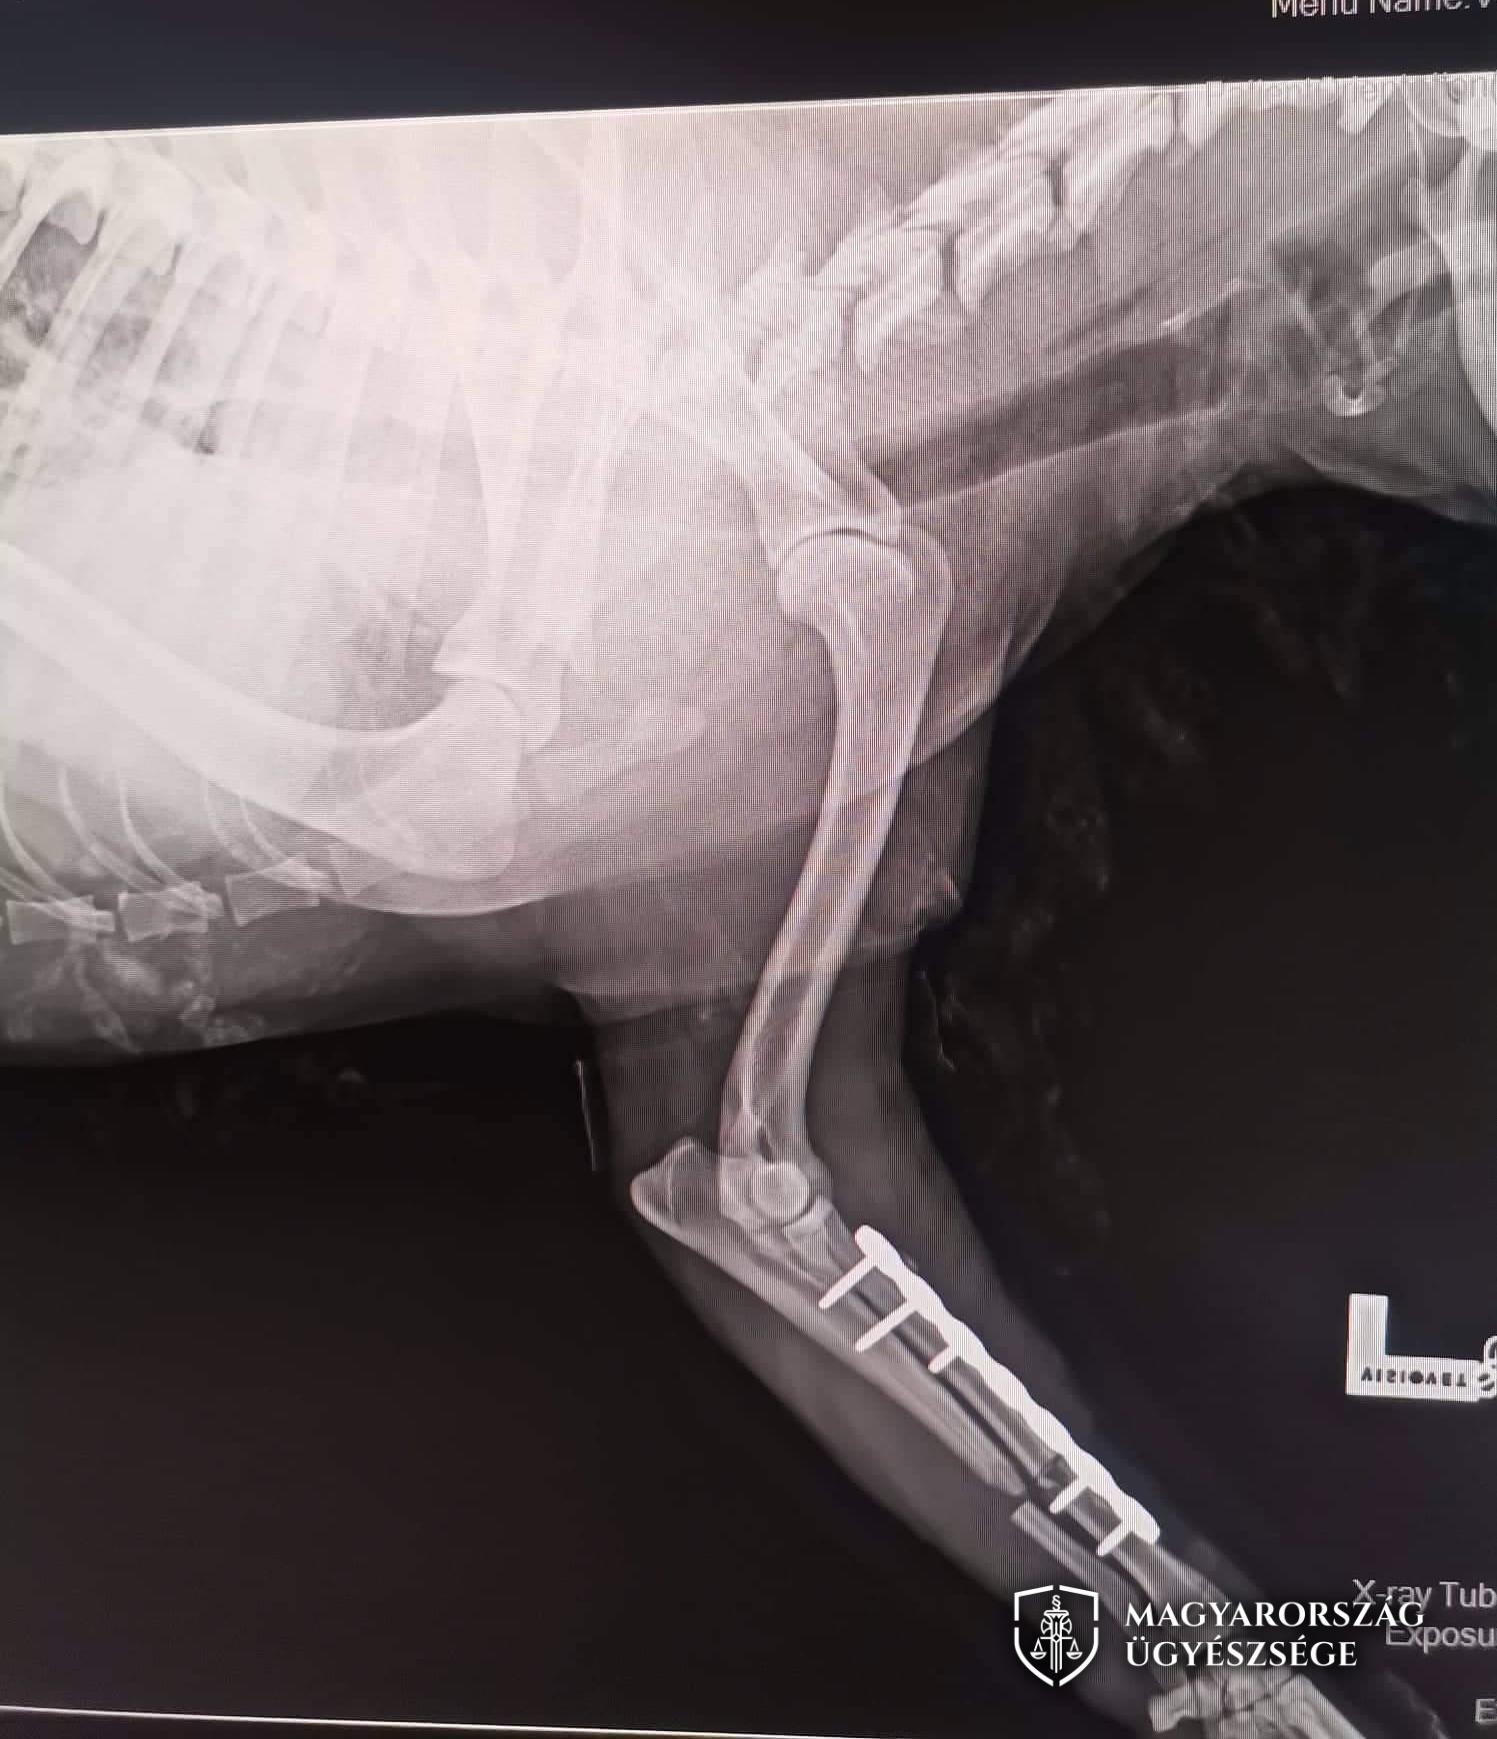

2022. novemberében is így történt, amikor a kutyák a vádlott juhait szűk helyre összeterelték, ezért a vádlott a kutyákra kiabált, és megindult feléjük. Az egyik kutya ennek hatására el is futott, azonban a másik eb nem reagált erre, ezért a vádlott az állatot egy karóval többször megütötte, amitől a kutya mindkét első lába eltörött. Mivel a törések súlyossága miatt a kutyát meg kellett műteni, és ettől a lába rövidebb lett, a bántalmazás az állat maradandó egészségkárosodását eredményezte, és különös szenvedést is okozott.

Fotók: Zalaegerszegi Járási Ügyészség